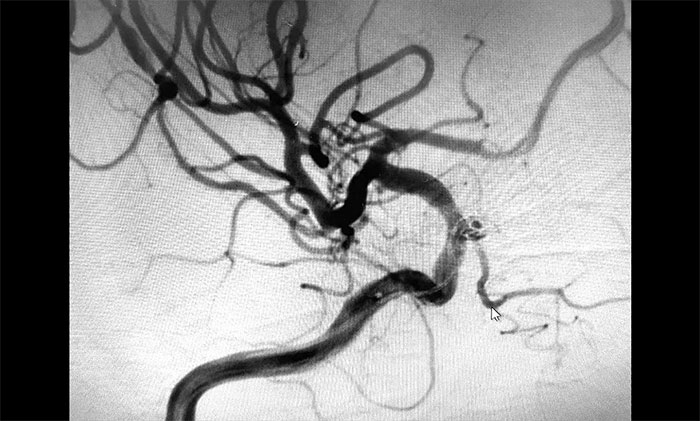

▲栓塞后,載瘤動脈血流通暢

術(shù)中,在微導(dǎo)絲的引導(dǎo)下將微導(dǎo)管頭端小心送入動脈瘤腔內(nèi),之后順著這個通路往動脈瘤內(nèi)填塞彈簧圈,造影顯示動脈瘤瘤內(nèi)造影劑明顯滯留,眼動脈(載瘤動脈)血流通暢。遂解脫彈簧圈并釋放支架,再次造影,支架覆蓋動脈瘤,貼壁良好。整臺手術(shù)歷時90分鐘順利完成,患者術(shù)后恢復(fù)情況良好。